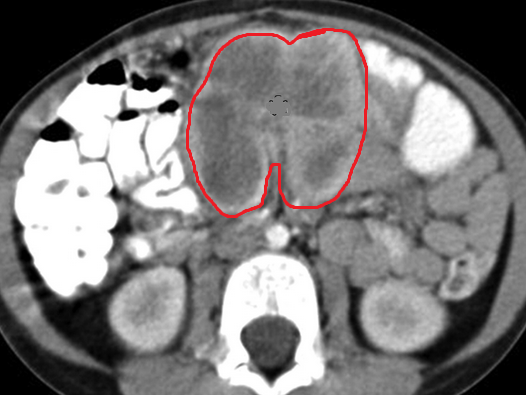

Large metastatic hepatic lesion, involving segments V, VI, VII, and part of VIII, 4.5 years after abdominoperineal resection of the rectum for poorly differentiated adenocarcinoma (Courtesy Dr. V. Penopoulos)